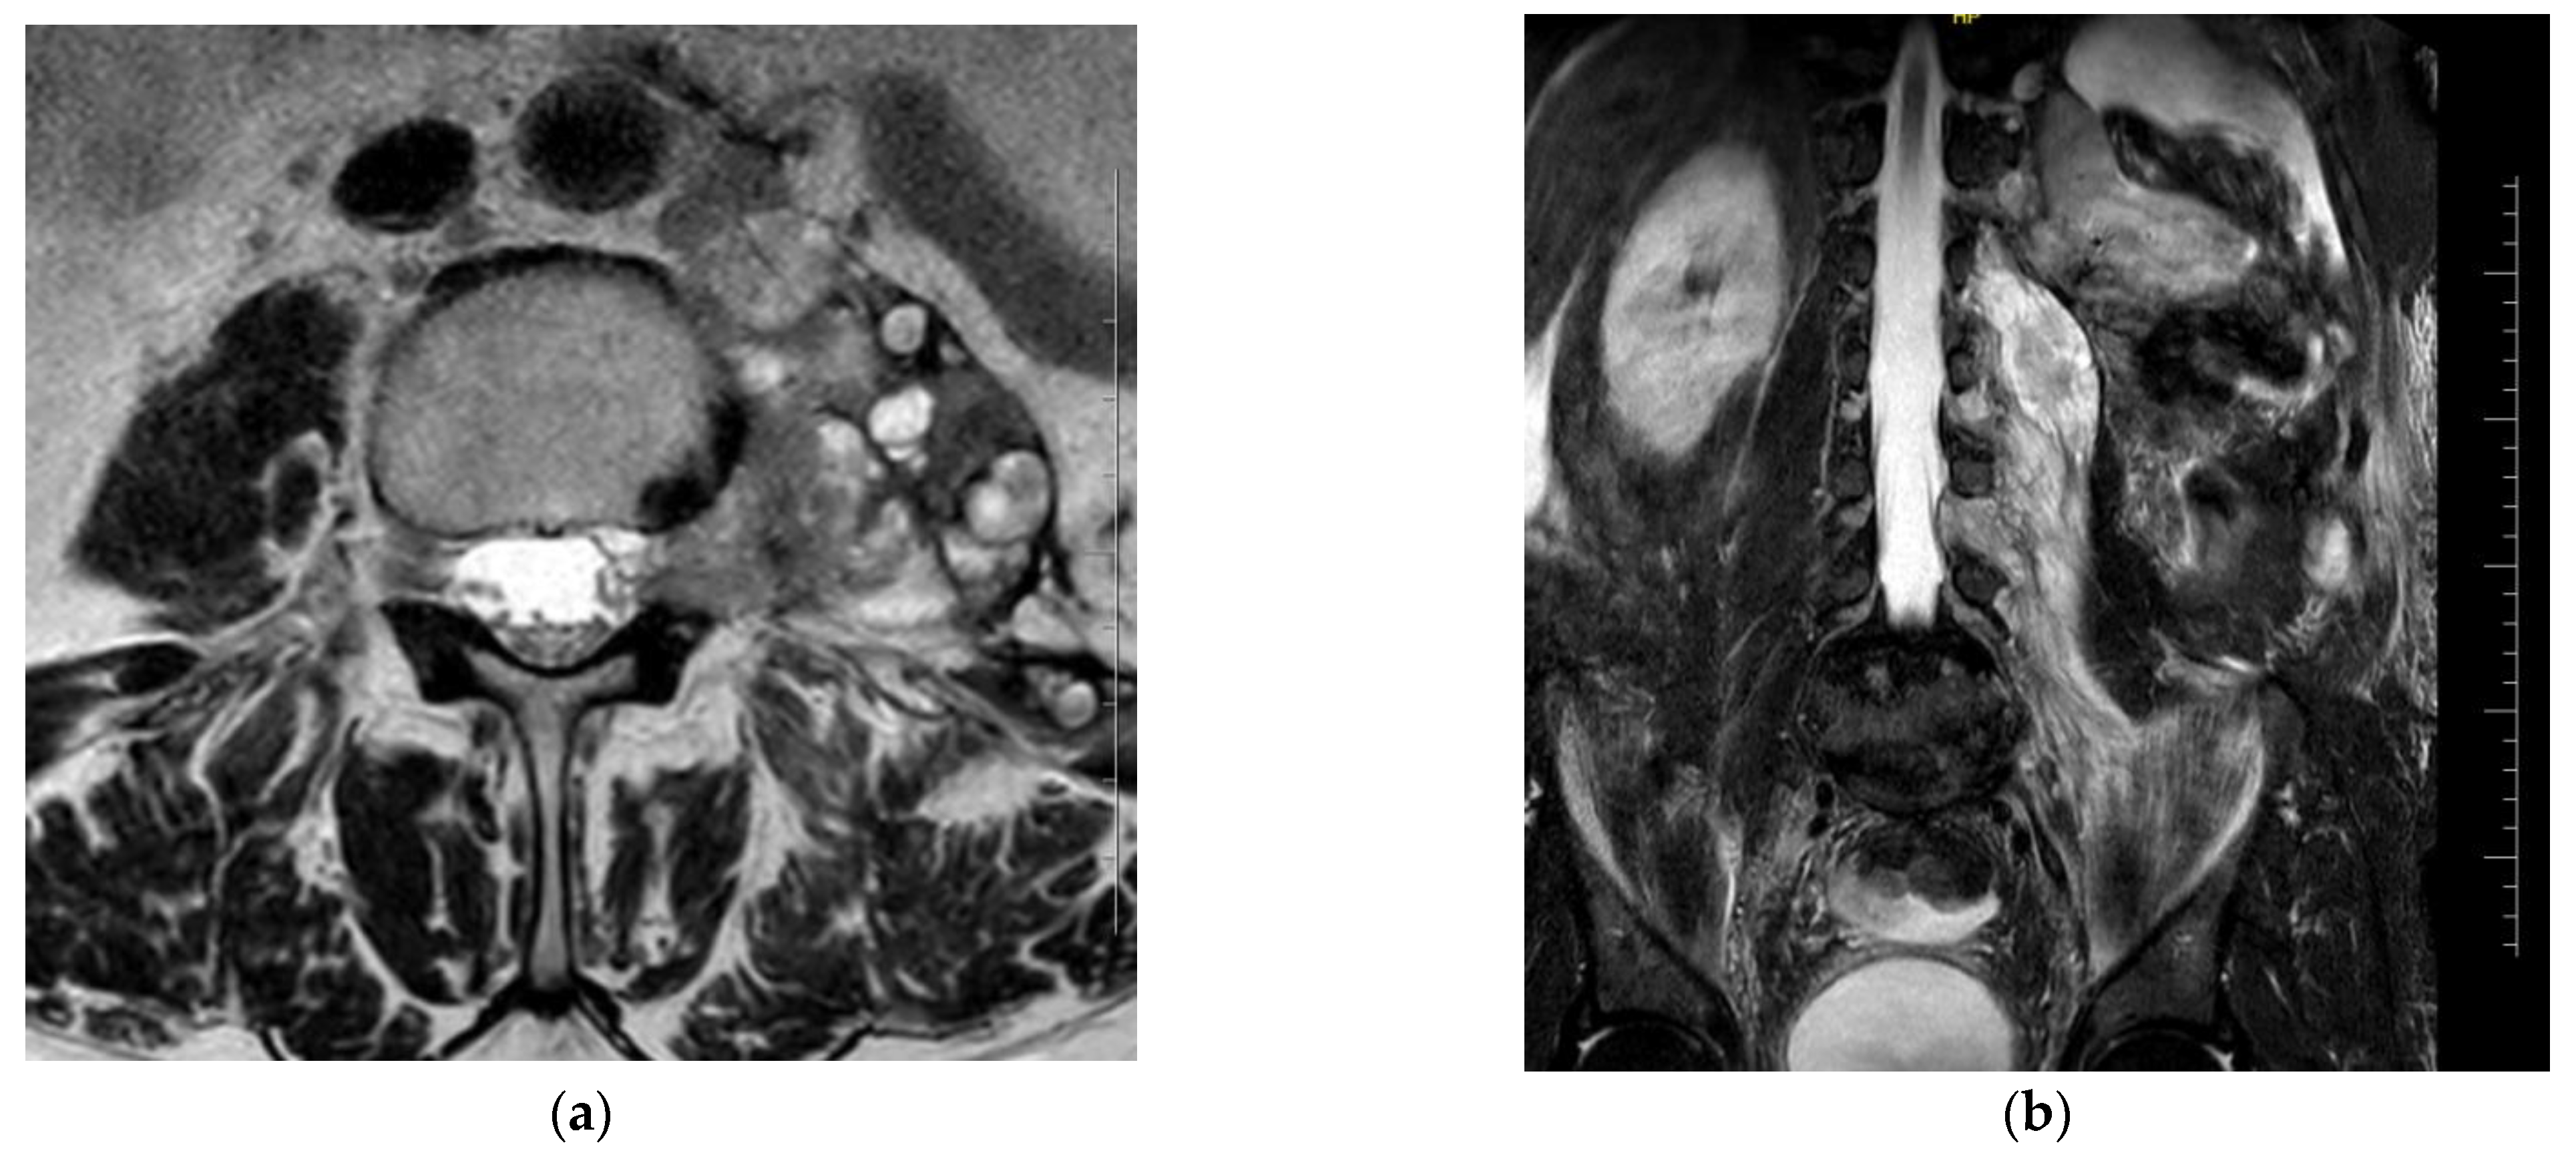

An imaging study (MRI of the lumbosacral spine) showed a 3.5 mm intradural lesion at Th 12 in the terminal part of the medullary cone on the left side—most likely a metastatic lesion. There was an extradural, paravertebral, and para-aortic conglomerate of lesions also involving the iliopsoas muscle and forming polycyclic masses extending for about 138 mm. These were lymph nodes and tumor metastases. At the L3–L4 level, there were visible metastases into the left intervertebral foramen with displacement and compression of the nerve roots. On the left side, there were spinal nerves among the conglomerate of the described lesions (Figure 1).

Figure 1.

MRI of the lumbosacral spine: (a) metastases into the left intervertebral foramen with displacement and compression of the nerve roots at the L3–L4 level, cross-section; (b) an extradural, paravertebral, and para-aortic conglomerate involving the iliopsoas muscle, longitudinal section.